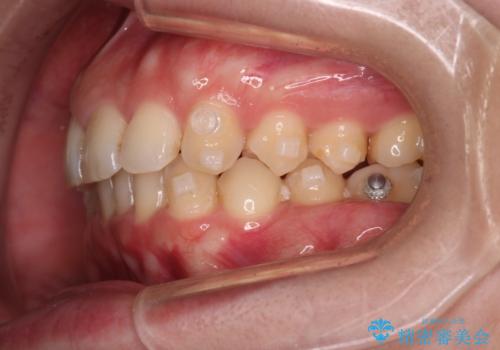

- 下の歯のがたつきを主訴に来院されました。

下の歯のがたつきと右の奥歯の噛みあわせ改善するために治療計画を立てることにしました。

右側臼歯部の咬合改善のために、臼歯部のみ部分的なワイヤー矯正を行い、咬合改善がみられてからインビザラインにて全体的な矯正を行なっていく治療計画を立てました。

噛み合わせをよくするために、ワイヤー矯正とインビザライン矯正のどちらの期間も必要な箇所にゴム掛けを行いながら治療を行いました。

下の前歯のがたつき改善にはIPR(歯と歯の間を削る処置)を行いました。